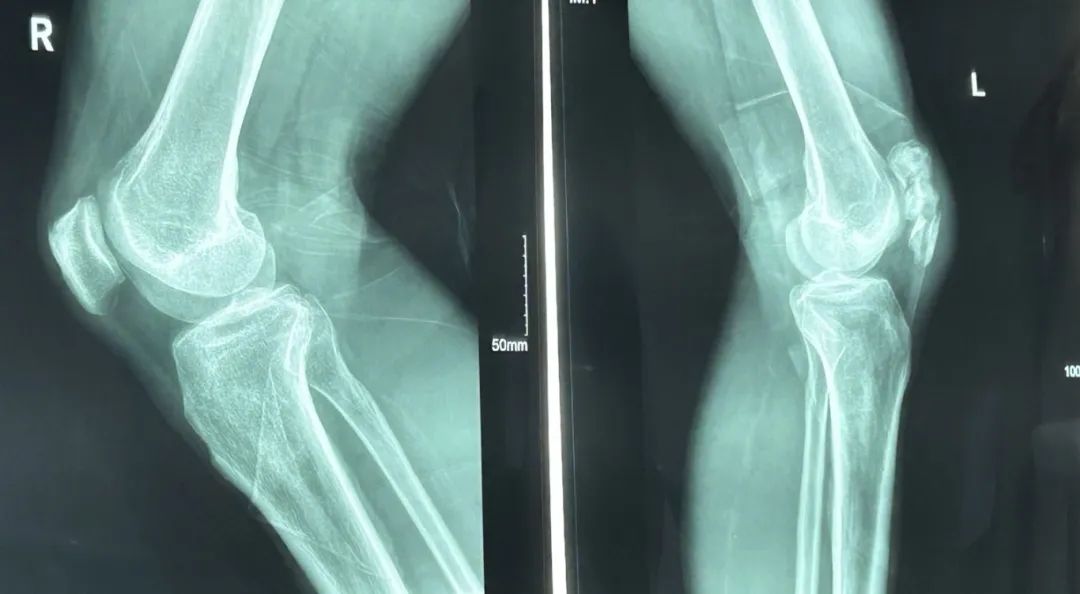

⇛四肢骨折:

●如肱骨、胫骨、股骨等部位的复杂骨折;

⇛关节周围损伤:

●肩关节脱位合并骨折、膝关节韧带损伤修复;